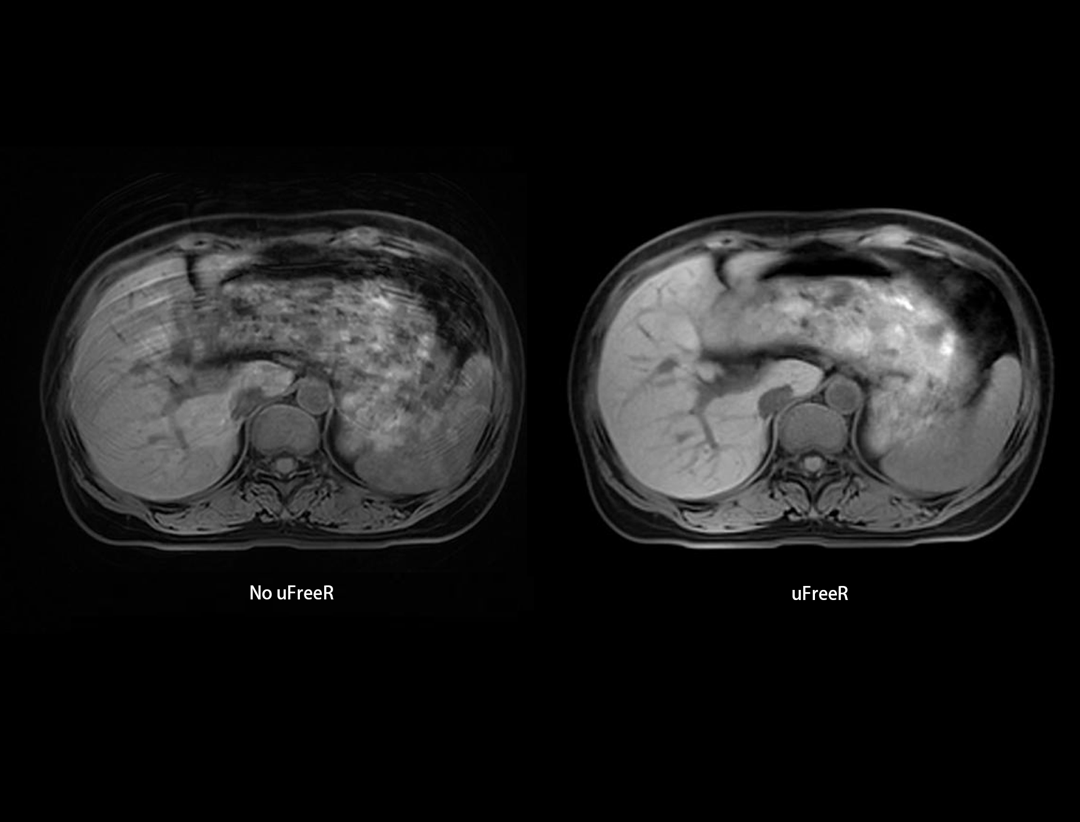

压缩感知·精准成像

精准成像

在提升扫描效率的同时,保持优异的解剖细节与对比度。